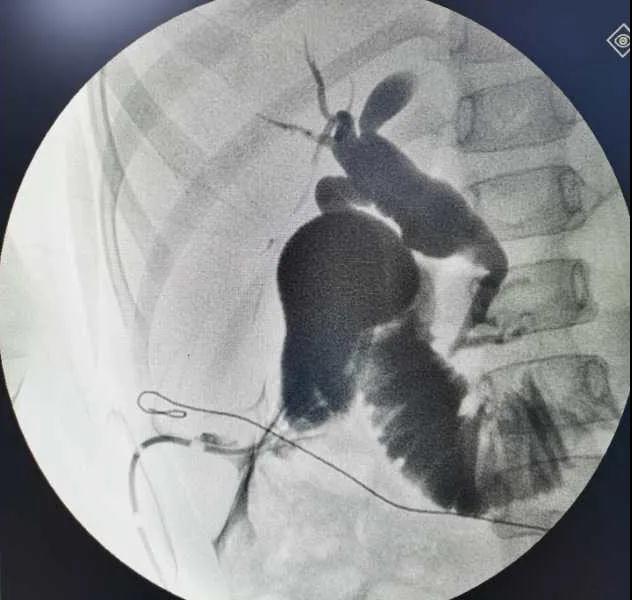

5月7日,西安國際醫(yī)學(xué)中心醫(yī)院小兒外科郭正團(tuán)教授團(tuán)隊(duì)成功為1名膽總管囊腫患兒進(jìn)行了腹腔鏡膽管造影 腹腔鏡膽總管囊腫切除 腹腔鏡肝管空腸吻合術(shù)。目前,患兒恢復(fù)良好,已正常進(jìn)食。

入院后,謝崇醫(yī)生積極為患兒完善術(shù)前準(zhǔn)備,MRCP(核磁共振膽道水成像)顯示該患兒為膽總管囊腫Ic型,有明顯的胰膽合流異常。面對(duì)復(fù)雜的病情,小兒外科郭正團(tuán)主任立即組織團(tuán)隊(duì)進(jìn)行術(shù)前討論,制定了完善的手術(shù)方案及應(yīng)急措施。

5月7日,一切準(zhǔn)備就緒,郭正團(tuán)主任主刀,帶領(lǐng)小兒外科團(tuán)隊(duì)進(jìn)行腹腔鏡膽管造影 腹腔鏡膽總管囊腫切除 腹腔鏡肝管空腸吻合術(shù)。術(shù)中,患兒膽總管與周圍肝動(dòng)脈及門靜脈粘連嚴(yán)重,給手術(shù)增加了難度。郭正團(tuán)主任沉著冷靜,操作嫻熟,完整剝離了膽總管囊腫及遠(yuǎn)端胰腺段膽管,肝總管與空腸完成了Roux-en-Y吻合,手術(shù)進(jìn)行順利。術(shù)后第2天,玲玲就可以下床活動(dòng);第6天,已正常飲食。